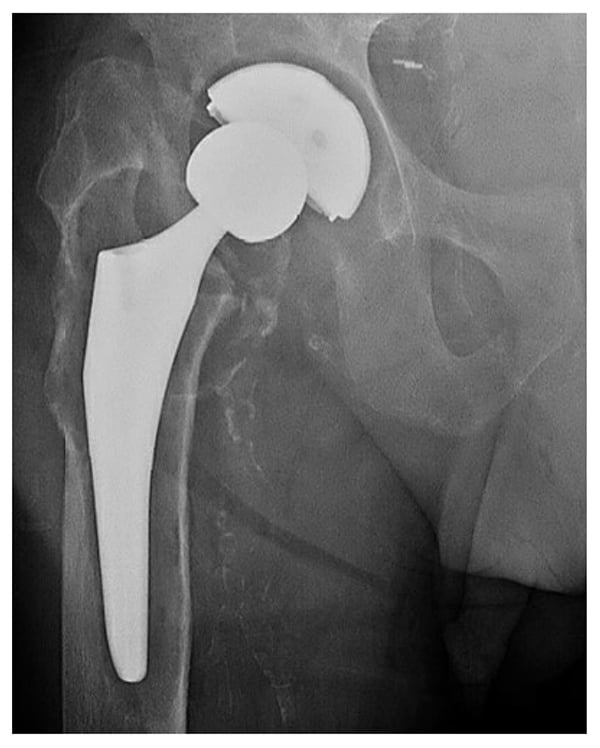

On examination, a 1.5-cm leg length discrepancy and limited hip flexion of 0 to 45° were noted. Radiographs showed septic loosening of the femoral and acetabular components with lytic areas around the acetabular component and around the proximal femur with bony remodeling (Fig. 1). Repeat aspiration was positive for Pseudomonas and methicillin-sensitive Staphylococcus aureus.

Figure 1: Preoperative radiograph shows THA with marked cystic osteolysis around the femoral component with subsidence, concerning for septic loosening. No fracture is identified. There is subluxation of the femoral head from within the acetabular component.